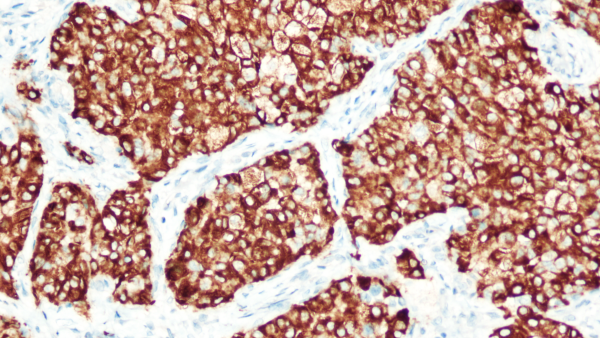

一、检测意义:肺癌治疗的"分子导航仪"肺癌是全球范围内最常见的恶性肿瘤,也是最主要的癌症致死原因,其中非小细胞肺癌(non-smallcelllungcancer,NSCLC)占肺癌80%-85%,其中约5.6%-7%存在间变性淋巴瘤激酶(AnaplasticLymphomaKinase,ALK)基因融合,在中国晚期NSCLC患者中ALK基因融合阳性率约为9.06%。ALK酪氨酸激酶抑制剂(tyrosinekinaseinhibitors,TKIs)靶向治疗可明显提高ALK基因融合晚期NSCLC患者的客观缓解率并延长无进展生存时间(progression-freesurvival,PFS),因此,ALK基因融合突变被称为“钻石突变”,其检测也被列为NSCLC病理标本的强推荐检测。关键临床价值​筛选克唑替尼/阿来替尼等靶向药物治疗获益人群;预测术后复发风险;指导围手术期治疗方案。二、适用人群:五大类患者精准覆盖根据《中国非小细胞肺癌ALK检测专家共识》:病理确诊为肺浸润性腺癌(包含腺癌成分)的患者;非腺癌晚期患者;术后复发转移病例​;年轻/不吸烟患者(ALK阳性率提升3倍);EGFR/KRAS阴性患者(排除其他驱动基因)。三、检测技术:Ventana-D5F3检测体系ALK基因融合可在多个分子水平上进行检测,包括荧光原位杂交(fluorescenceinsituhybridization,FISH)在DNA水平上检测ALK易位、即时荧光定量聚合酶链反应(realtimepolymerasechainreaction,RT-PCR)检测ALK融合mRNA、免疫组织化学(immunohistochemistry,IHC)检测ALK融合蛋白表达以及二代测序(next-generationsequencing,NGS)技术检测DNA水平上的易位序列或mRNA水平上的融合序列。目前,我国NMPA批准了4个技术平台的ALK基因检测伴随诊断试剂,包括ALKVentana-D5F3IHC、FISH、RT-PCR及NGS检测平台。研究结果显示,这4个技术平台检测试剂均具有较高的灵敏度和特异度。根据临床具体情况及实验室条件,我中心选择ALKVentana-D5F3IHC检测平台,近日正式开展工作。该平台的核心优势​如下:抗体特异性:D5F3抗体灵敏度95%-100%,特异度99%平台优势:全自动Ventana免疫组化染色系统判读标准:阳性:≥10%肿瘤细胞膜/胞质强染色阴性:无染色或<10%弱染色典型检测结果示例​图:肺腺癌ALK(Ventana-D5F3)染色呈阳性,左为中分化腺癌,右为低分化腺癌四、参考文献中国非小细胞肺癌ALK检测模式真实世界多中心研究专家组,中华医学会病理学分会分子病理学组.中国非小细胞肺癌ALK检测临床实践专家共识.中华病理学杂志,2019;48(12):913-920中国医师协会肿瘤医师分会中国医疗保健国际交流促进会肿瘤内科学分会.间变性淋巴瘤激酶酪氨酸激酶抑制剂治疗非小细胞肺癌指南(2025版).中华肿瘤杂志,2025;47(4):283-297孙伟臻;周宇桁;林耀彬等.ALK融合阳性非小细胞肺癌新辅助靶向治疗的进展.中国肺癌杂志,2024;27(11):849-854.李琳;李文才;武春燕等.中国晚期非小细胞肺癌间变性淋巴瘤激酶(ALK)重排检测的真实世界数据(RATICAL):一项全国多中心回顾性研究.癌症,2025;44(05):231-242.PoeiD,AliS,YeS,etal.ALKinhibitorsincancer:mechanismsofresistancetherapeuticmanagementstrategies.CancerDrugResist.2024;7:20.VoenaC,AmbrogioC,IannelliF,etal.ALKincancer:fromfunctiontotherapeutictargeting.NatRevCancer.2025;25(5):359-378.备注:本文在成稿后经由元宝大语言模型进行语言润色与逻辑优化,旨在提升表达的准确性与流畅性,核心观点与内容均由作者独立完成。‌‌